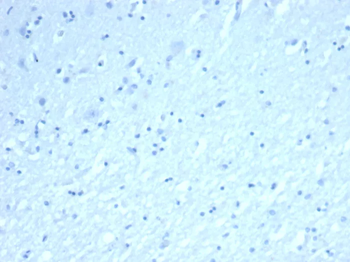

IHC analysis of formalin-fixed, paraffin-embedded human brain. Negative tissue control using rINHA/6919at 2 ug/ml in PBS for 30 min RT. HIER: Tris/EDTA, pH9.0, 45 min. 2°: HRP-polymer, 30 min. DAB, 5 min.